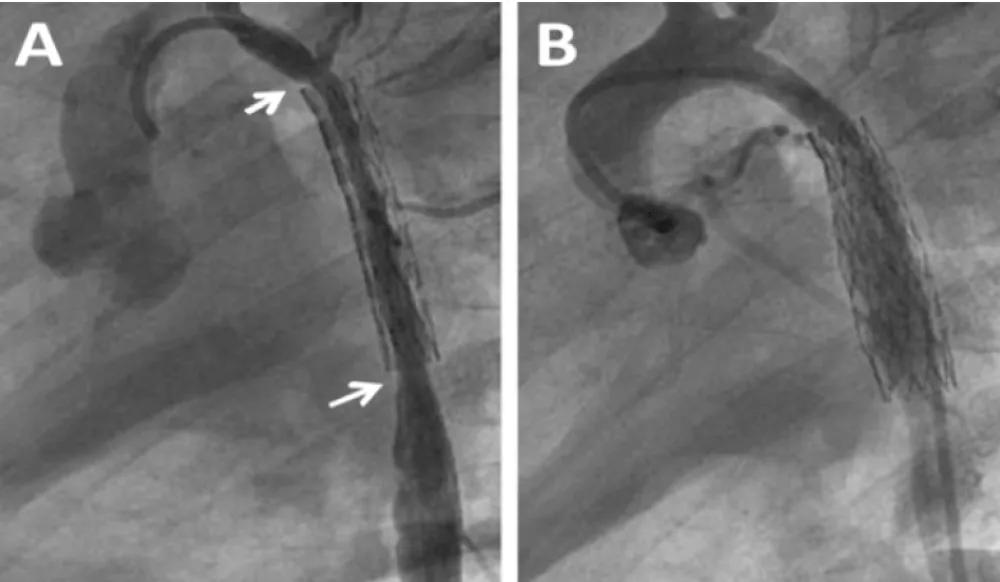

Cardiac catheterization and aortogram for stent angioplasty were performed showing similar diameters to those described in the CT (Figure 2A and B). Pressure measurements are shown in Table 1. The peak systolic gradient across the coarctation decreased markedly after stenting with a 29 mm long Genesis XD stent delivered over a 5F 5 by 30 mm balloon catheter. Control aortogram showed a well expanded stent with a uniform 5 mm diameter similar to that of the descending aorta.

Figure 2: Stenting Procedure for Recurrent Coarctation at age 5 months. A: Pre stenting aortogram shows the coarctation and mid aortic stenosis; B: Post stent angioplasty depicts uniform diameter of the descending aorta from the coarctation site up to the diaphragm level.